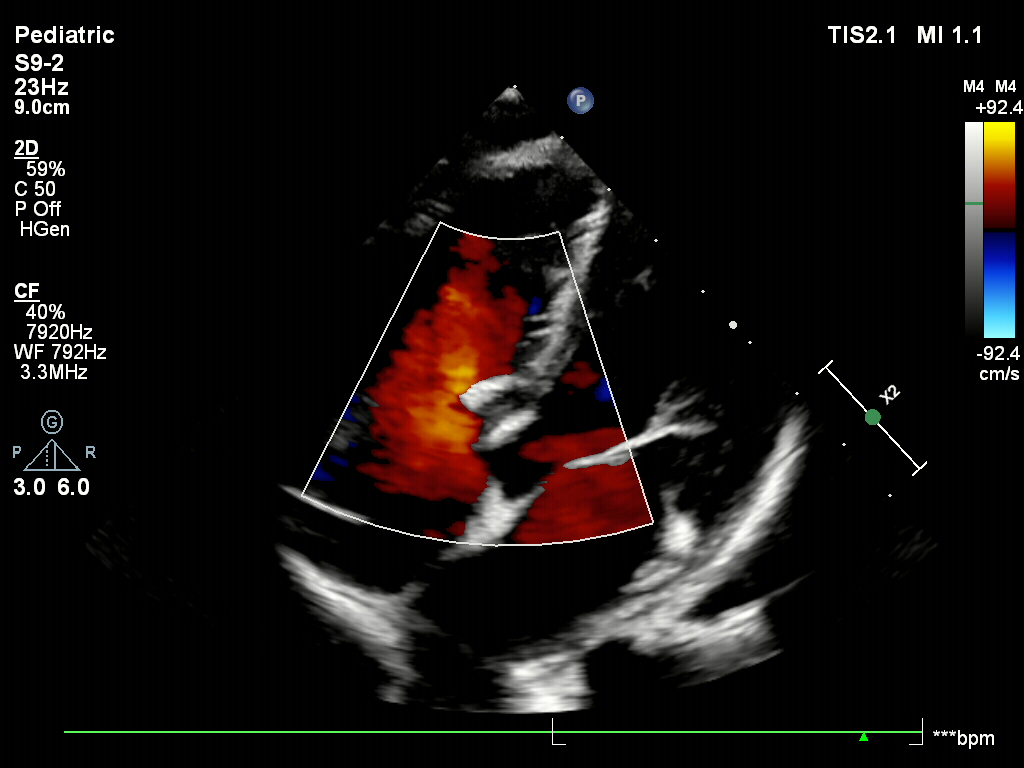

术后1个月超声

封堵器稳定夹持在室间隔两侧,无残余分流

患者是6岁的儿童,心脏尚处于发育阶段,植入金属封堵器可能面临着传导阻滞等不良事件的风险。此外,缺损部位距离三尖瓣较近,使用金属封堵器可能会磨蚀心脏组织。因此,为减少远期并发症发生的可能,减轻心理负担,并消除金属植入物带来的远期学业事业上的影响,选用无金属植入物的全降解封堵器。全降解封堵器不包含任何金属植入物,并实现1年有效降解。降解产物安全,为水和二氧化碳,降解后跟随人体代谢排出体外。此外,全降解封堵器材质柔韧,对人体组织有较强的自适应性,大大降低组织磨蚀风险。手术行经股入路,术中造影测量膜部瘤基底和破口大小,膜部瘤基底11.6mm,破口大小4.7~5.4mm,大于院内超声测量。由于该缺损距离三尖瓣距离较近,不宜选伞过大,因此根据术中造影测量的破口大小,选用ABFDQ-II 08全降解封堵器封堵破口并盖住基底。术后即刻超声下观察,封堵器两盘稳定夹持在室间隔两侧,周围瓣膜组织未受影响,无残余分流,封堵成功。术后一个月复查,超声显示封堵器无位移,稳定骑跨于室间隔两侧,无残余分流。